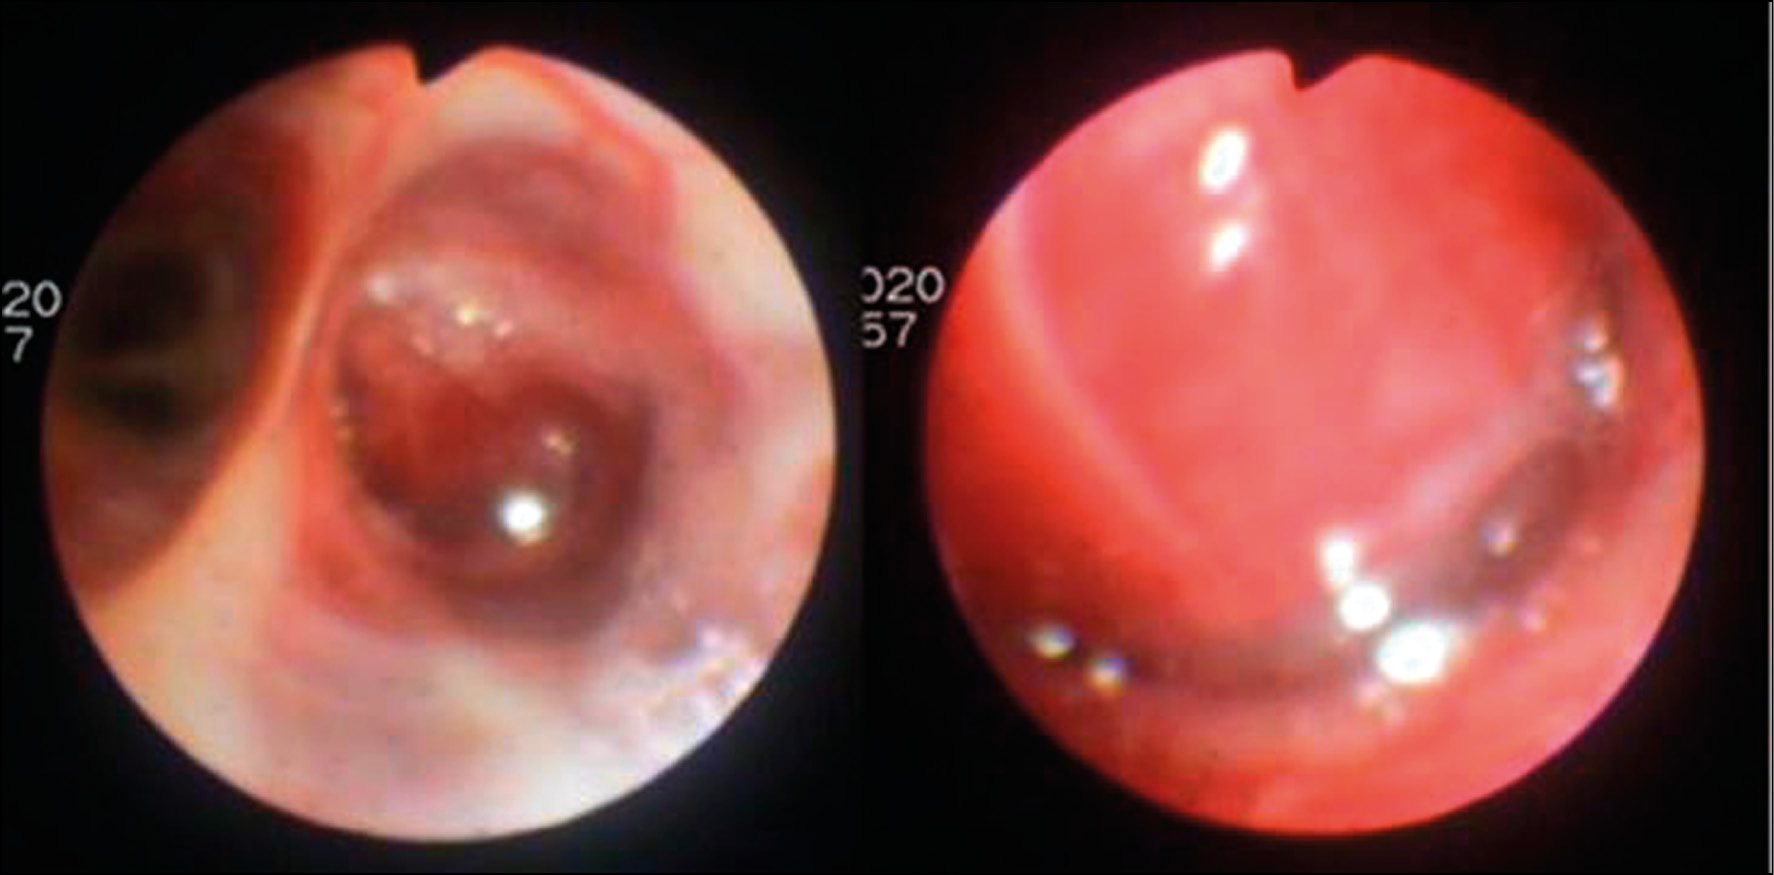

Changes were characteristic of bronchocele caused by neoplastic bronchus obstruction. Fibrobronchoscopy with biopsy was also performed. Bronchoscopy revealed a rounded lesion of the B4 ostium, which completely covered the bronchial lumen (Fig. 4). The lesion is inactive and woundable on contact, and the mucous membrane on the surface is hyperemic and edematous. The biopsy results revealed that the histological presentation of the lesion corresponded to a typical carcinoid. The immunohistochemical study revealed that tumor cells intensely expressed CD56, but not TTF1. The Ki67 proliferative activity index was 2%.

Fig. 4. The same patient. Fibrobronchoscopy: the formation of the B4 mouth on the right, completely covering the lumen of the bronchus.